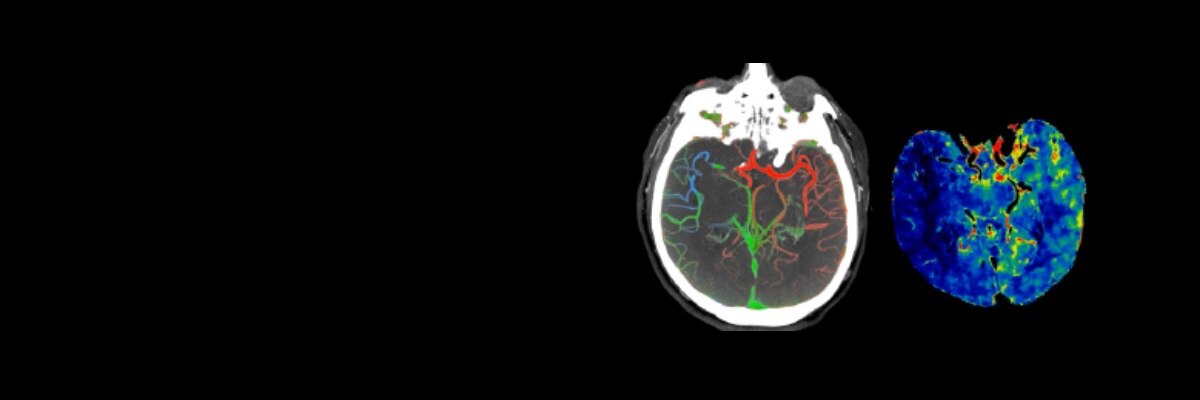

РЕШЕНИЯ В ОБЛАСТИ ЛЕЧЕНИЯ ИНСУЛЬТА